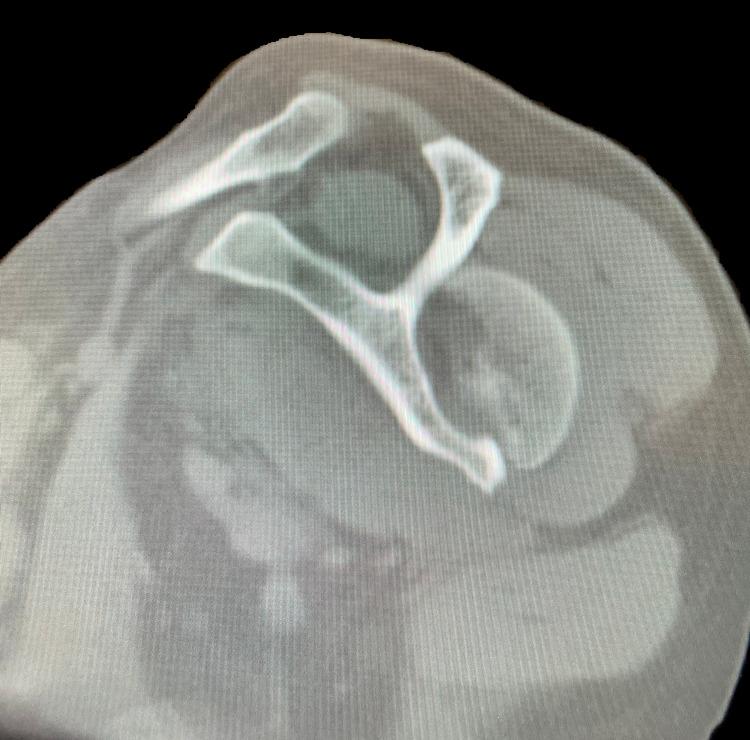

This report presents a previously undescribed case and treatment of bilateral four-part proximal humerus (PH) fracture-dislocations presented in a 61-year-old Caucasian male patient following a first-time seizure episode. The patient was treated with bilateral reverse total shoulder arthroplasty due to pre-existing glenohumeral arthritis and rotator cuff atrophy. The surgery was successful, and the patient's postoperative recovery was uneventful. Fractures of the proximal humerus are a relatively common adult osteoporotic fracture; however, posterior fracture-dislocations of the PH, frequently related to motor vehicle accidents, seizures, or electrical shock, are remarkably scarce. A treatment algorithm for these injuries is lacking.

本报告介绍了一例此前未被描述的双侧四部分近端肱骨(PH)骨折脱位病例及治疗情况,该病例发生在一名61岁的白种男性患者首次癫痫发作之后。由于患者术前存在盂肱关节炎和肩袖萎缩,故对其进行了双侧反式全肩关节置换术。手术成功,患者术后恢复顺利。近端肱骨骨折是一种相对常见的成人骨质疏松性骨折;然而,PH的后脱位骨折,常与机动车事故、癫痫发作或电击有关,却极为罕见。目前尚缺乏针对这些损伤的治疗方案。